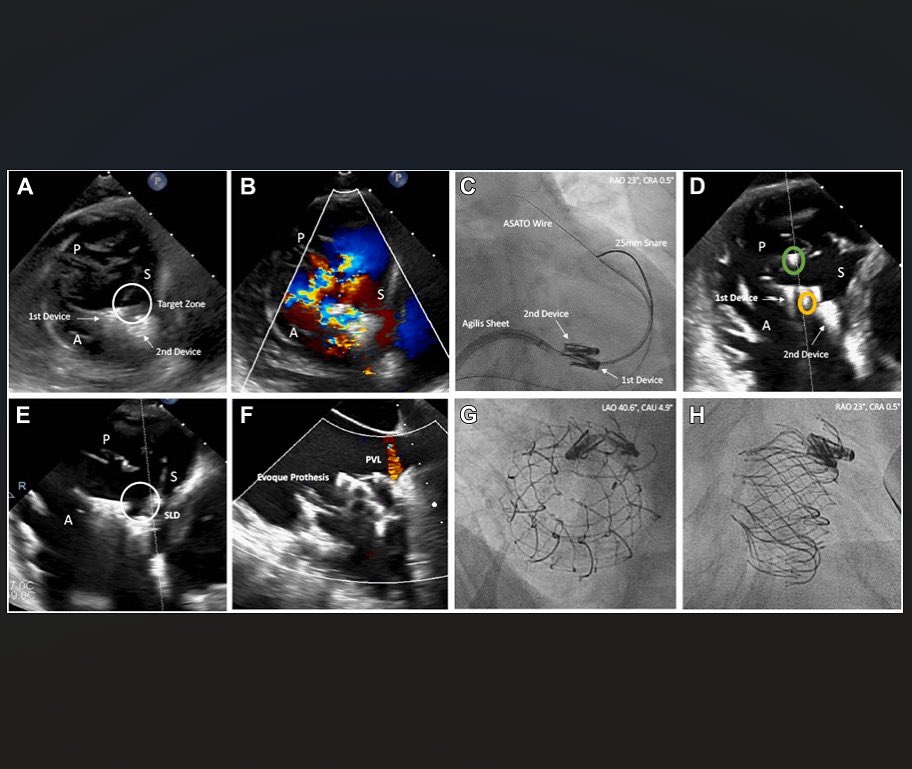

We are proud to announce that the cardiology team at Uniklinik Düsseldorf successfully performed the first interventional transfemoral tricuspid valve replacement this week! A huge thank you to the entire team!